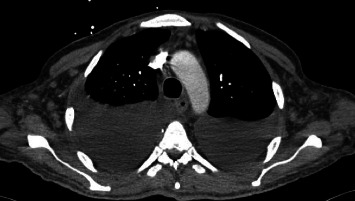

Abstract Image

Kaposi sarcoma (KS), an angioproliferative neoplasm driven by human herpesvirus 8, predominantly affects patients with acquired immune deficiency syndrome (AIDS) or those on immunosuppressive therapy. Gastrointestinal involvement in KS is underreported, with limited literature highlighting its clinical significance and morphological diversity on endoscopy. This case report illustrates the complexities of diagnosing and managing gastrointestinal KS in an AIDS patient who presented with upper gastrointestinal bleeding. The diagnosis was established through the characteristic endoscopic appearance of the lesions, supported by histopathological confirmation. This case emphasizes the variable endoscopic manifestations of KS, ranging from linear ulcers to nodular lesions, and underscores the necessity for heightened clinical vigilance and multiple deep biopsies to avoid false-negative results. Treatment options, primarily palliative, include highly active antiretroviral therapy, chemotherapy, and radiation, yet the prognosis remains poor with high short-term mortality. This report contributes to the sparse literature on gastrointestinal KS, advocating for increased awareness and early intervention to potentially improve outcomes in this patient population.